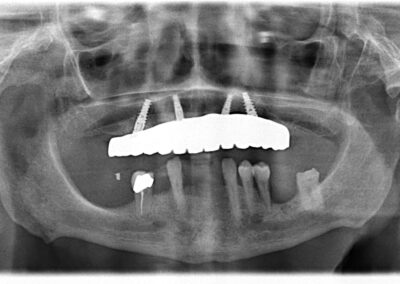

All-on-4®️ and Implant Dentistry

Dr. Norman D. Knowles is a leading expert in implant dentistry with over two decades of experience. Our practice offers state-of-the-art implant solutions to restore missing teeth and enhance your smile. Whether you need a single tooth replacement or a full-mouth restoration, we are dedicated to providing you with the highest quality care and achieving optimal results.

- Cost-Efficient: The All-on-4® treatment concept provides a graftless solution, making it a cost-effective option for patients seeking a fixed full-arch prosthesis.

- Immediate Results: Patients can receive a new set of teeth on the same day as surgery, reducing the waiting time and providing immediate aesthetic and functional benefits.

- Patient Satisfaction: With a high satisfaction rate of 95% and an impressive implant survival rate of 98%, the All-on-4® treatment concept offers a safe and predictable surgical protocol.